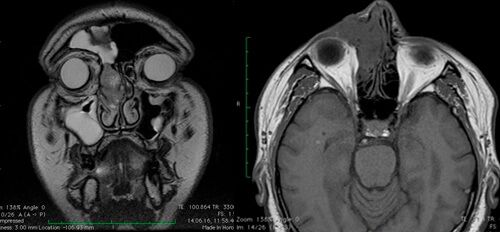

В диагностике инвертированных папиллом ключевое место занимают лучевые методы исследований

- компьютерная томографии

- магнитно-резонансная томографии (с контрастом по назначению врача).

Ценность КТ – материалов состоит в возможности точной оценки границ опухоли, что позволяет определить стадию процесса и тактику дальнейшего ведения больного. МР-данные позволяют дифференцировать активный воспалительный процесс в пазухах от фиброзной и рубцово-измененной ткани. Введение контрастного препарата повышает яркость свечения воспаленной слизистой оболочки.